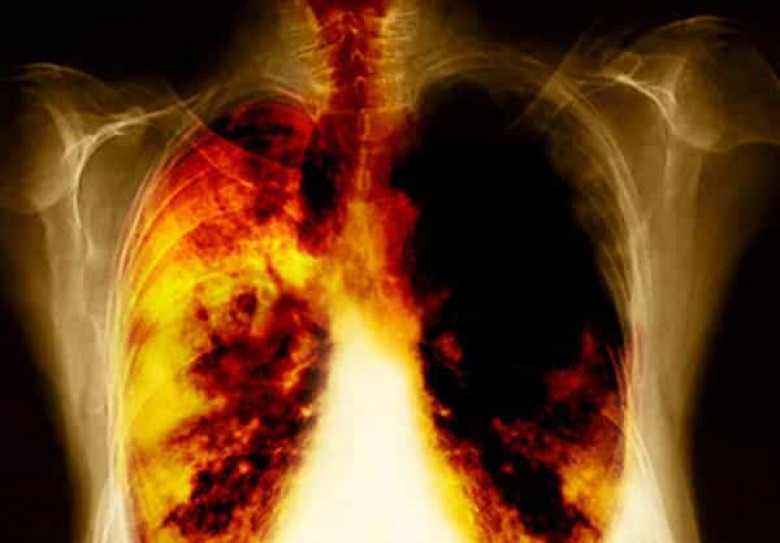

5 ախտանշան, որ կարող են հուշել թոքերի քաղցկեղի զարգացման մասին